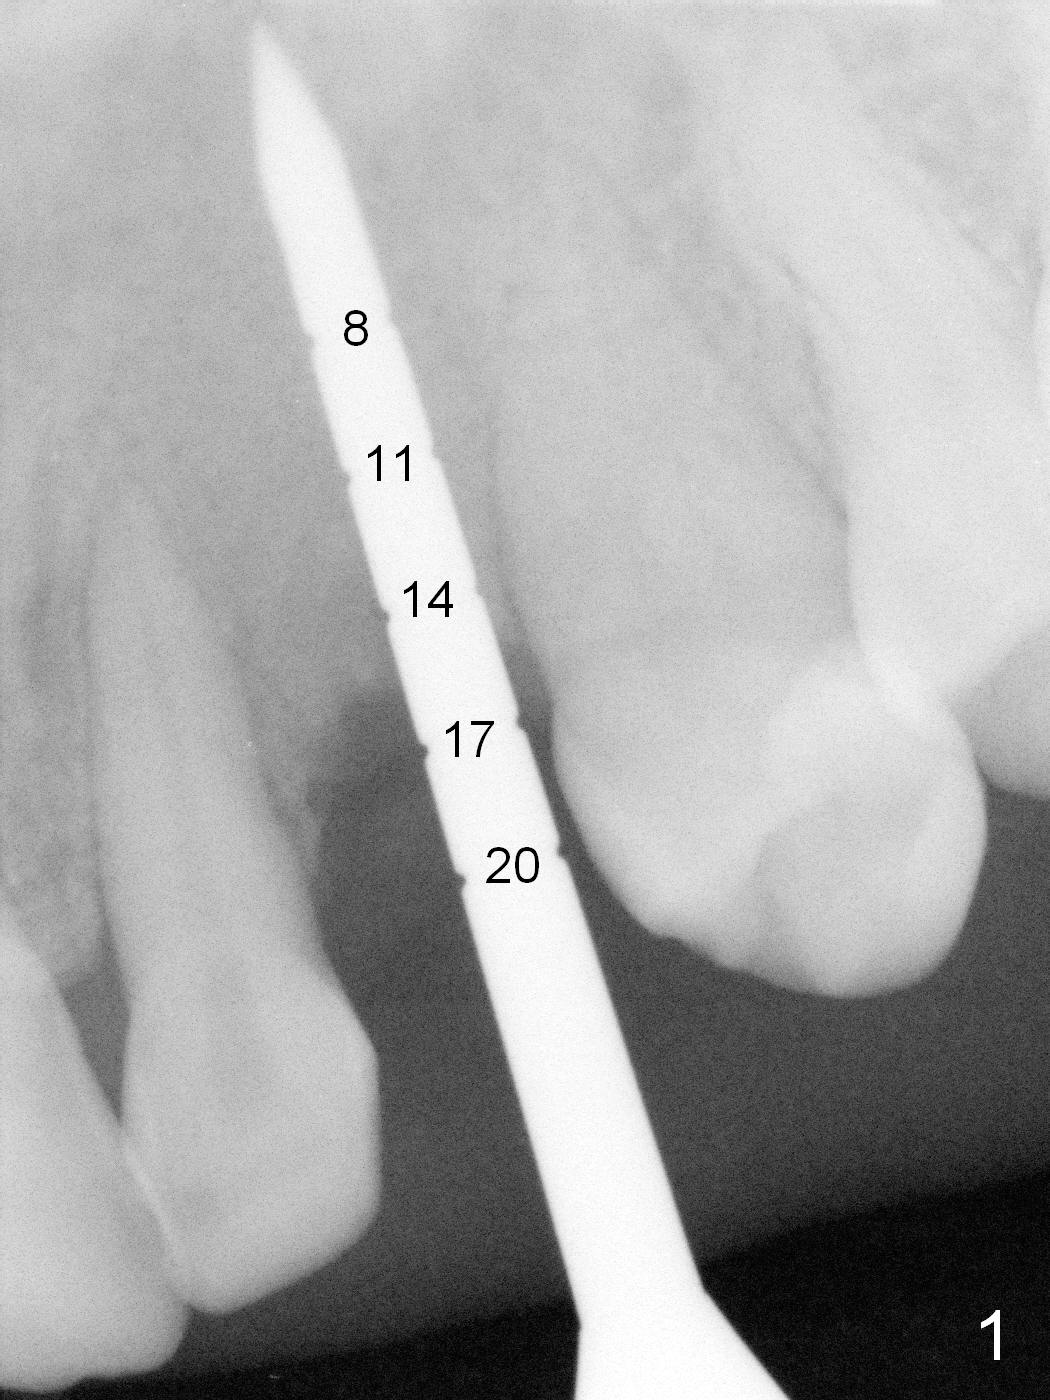

The ridge looks wide clinically 4 months post implant removal and socket preservation. In fact, the graft bone is soft and the ridge is narrow after incision. It appears that an angled 1 piece implant is an indication. A 1.2 mm pilot drill is used to start osteotomy. At approximately 17 mm, the patient feels pain. The nasal floor perforates? A 2 mm osteotome is utilized to enlarge the osteotomy. At 17 mm, the osteotome is stable (Fig.1), but the nasal floor appears out of view. Review of the preop PA shows that the distance between the gingival margin and the nasal floor (arrowheads) is ~22 mm (Fig.2). It should be safe and necessary to place a 3x20 mm 1-piece implant with 15° angulation. Insertion torque is between 40 and 45 Ncm.